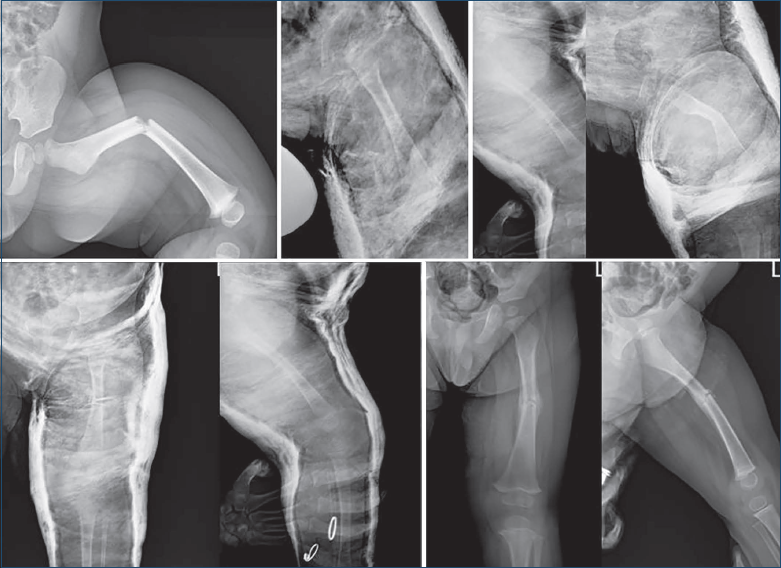

Le fratture di femore in età pediatrica rappresentano a tutt’oggi un grande impegno per lo specialista ortopedico. Il trattamento è orientato principalmente dall’età, con una preferenza per l’incruento fino a 5 anni e per il chirurgico dai 6 anni in su. È evidente che, nonostante questa indicazione di massima, possono esserci delle variazioni legate al pattern di frattura, al peso del paziente, all’esperienza e preferenza del chirurgo. Fino a 6 mesi di età il trattamento consigliato è il tutore di Pavlik 17. Applicato immediatamente risulta idoneo a ridurre il dolore, stabilizzare il femore e provvedere ad ottenere una rapida guarigione, confidando anche sulla capacità di rimodellamento a questa età. Tra i 6 mesi ed i 5 anni di età il trattamento convenzionale prevede l’applicazione della trazione e dopo circa 2 settimane il confezionamento di un gesso tipo pelvi podalico 18 fino alla consolidazione. Altra ipotesi di trattamento è l’immediato confezionamento dell’apparecchio gessato, metodica preferita dagli autori. Come riportato da Buehler et al. 19, tale metodica determina un 95% di successi; Yandow et al. 20 riportano risultati confrontabili al trattamento con trazione e successivo gesso, ad eccezione del fatto che sono riportati in letteratura episodi di paralisi peroneale, una sepsi, ed un caso di fat embolism, una maggiore frequenza di viziose consolidazioni ed esiste un significativo aumento di costi in termini di degenza ospedaliera nel trattamento con trazione (Fig. 3).

Al contrario l’immediato trattamento in gesso si dimostra semplice, sicuro e non richiede particolari competenze, come riportato da Infante et al. 21, presentando tuttavia lo svantaggio del rischio di sindrome compartimentale, ridotta motilità ed impossibilita ad esplorare i tessuti molli sottostanti con possibilità di insorgenza anche di piaghe da decubito. Un ulteriore limite è rappresentato dalla necessità di dover effettuare controlli radiologici seriati per poter correggere eventuali perdite di riduzione in gesso e dunque la necessita di rivedere frequentemente il paziente (Fig. 4).

Figura 3. Paziente trattato con Gallow traction fino alla consolidazione in varo ed accorciamento.

Figura 4. Paziente di anni 5 trattato immediatamente con apparecchio gessato pelvipodalico con perdita di riduzione alla radiografia a 7 gg che ha reso necessario il rinnovo dell’apparecchio gessato per correggere la deformità e mantenuto fino alla consolidazione.